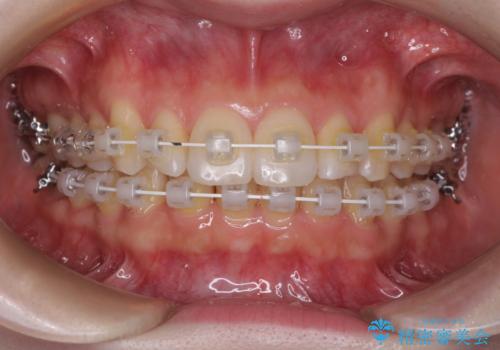

- 矯正装置

- 審美装置

半年もせずにインビザラインを全く使用することができなくなってしまったので、治療開始から1年ほどでワイヤー矯正へ変更することとなりました。

ワイヤー矯正へ変更してからはあっという間に治療が進み、1年弱で終えることができました。